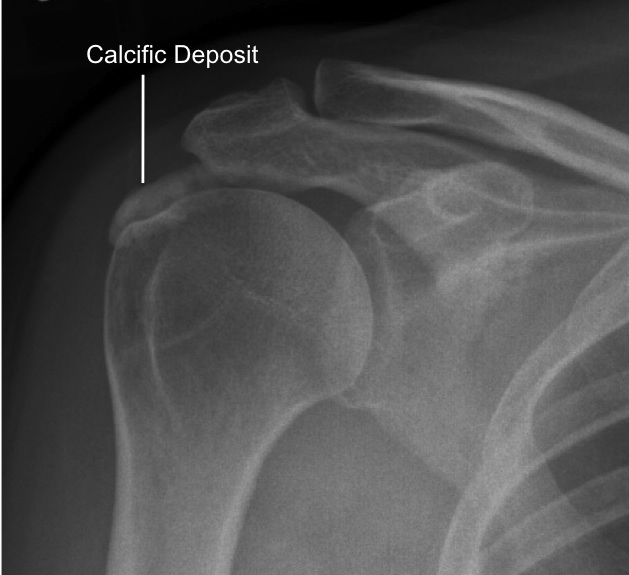

Cause Of Calcium Deposits In Shoulder . calcific tendonitis is a condition where deposits of calcium build up in a tendon or. calcific tendonitis (or tendinitis) occurs when calcium deposits build up in your muscles or tendons. calcific tendinopathy (ct) of the shoulder is a common, painful condition identified by the existence of calcium deposits in the rotator cuff tendons. Although this can happen anywhere in the body, it usually occurs in the rotator cuff. calcific tendinitis of the shoulder, classified as enthesopathy, is a. a calcium deposit, or calcification, in your shoulder can cause pain and discomfort when you move. calcific tendinitis of the shoulder is often an acutely painful condition due to the presence of calcific deposits inside within the.